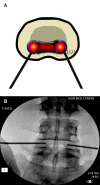

Figure 23.

Figure 23.. A and B, Biacuplasty® Procedure With Cooled Radiofrequency

The entry point is at the posterolateral annulus and the thermal element is guided through the introducer at the annular-nuclear junction with the final position in the posterior aspect of the disc.